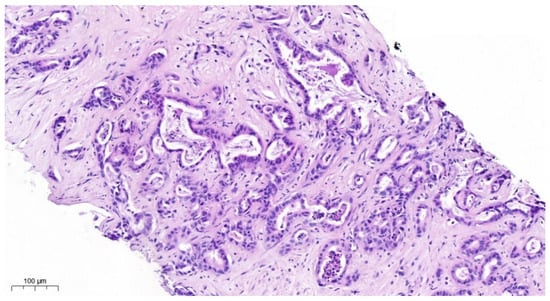

Overall, 25 clinically diagnosed intrahepatic cholangiocarcinomas (Figure 1) or Adeno-CUPs of six women (24%) and 19 men (76%) at the ages of 40 to 83 years (mean: 64 years, median: 63 years) were analyzed.

Figure 1. HE staining. iCCA consists of infiltrating glands in an abundant desmoplastic; fibrous stroma glands are lined by atypical cuboidal cells with varying degrees of pleomorphism intraluminal cellular debris.